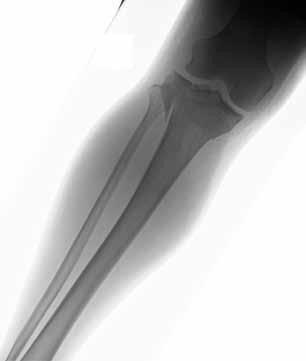

are the radiographs of a 23-year-old man who fell from a height and sustained an isolated injury to his right leg. Which of the following is a useful surgical technique to optimize alignment during intramedullary nailing?